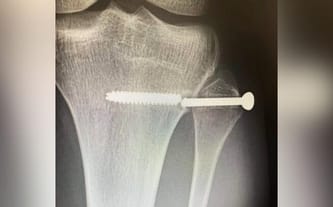

Stan po operacji stabilizacji stawu strzałkowo piszczelowego